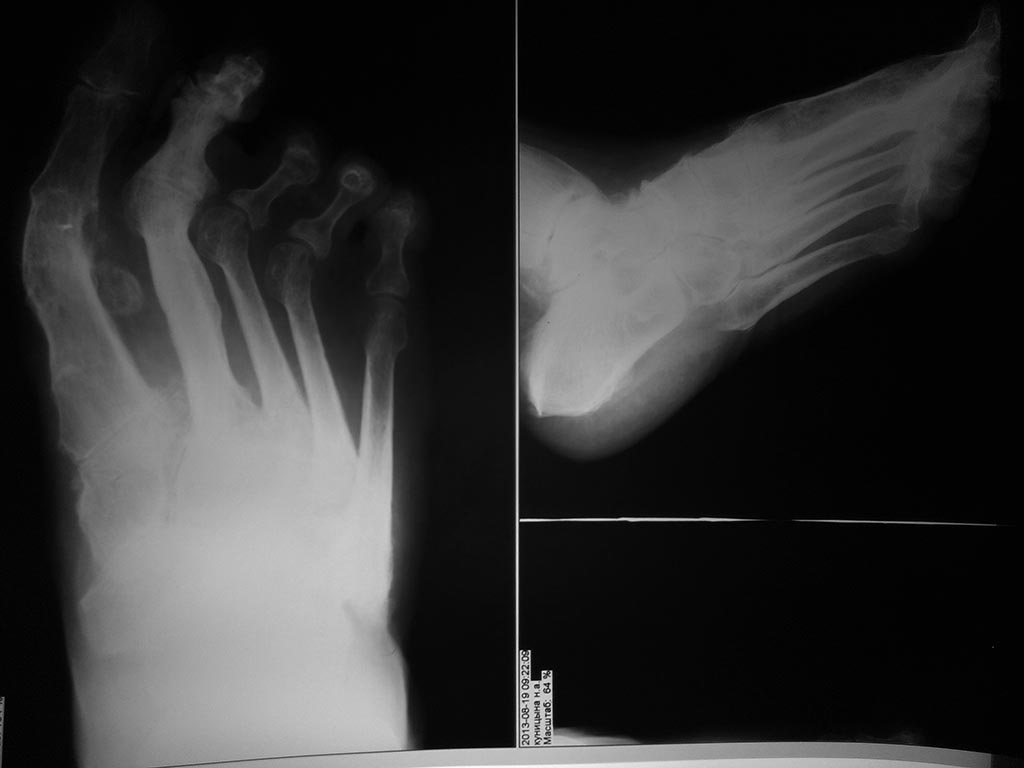

[Ortho] повторная операция при деформации стопы

Всем здравствуйте! Проблема повторных операций на стопе

становится все актуальнее. Женщина после артродезирования 1 ПФС и

неизвестного объема вмешательства на втором луче (но в обоих были спицы

трансартикулярно) испытывает сильные метатарзалгии, второй палец

ригидный и намного длиннее первого (прошу прощения за отсутствия фото in

vivo!!!)... Какой объем операции на втором луче и других посоветовали бы

подологи с учетом артрозов второго пальца, подвывихов 3-4 ПФС? Заранее

спасибо!!!